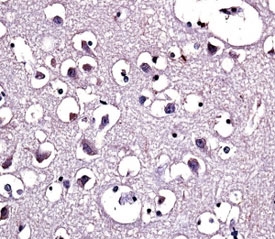

LPL encodes lipoprotein lipase, which is expressed in heart, muscle, and adipose tissue. LPL functions as a homodimer, and has the dual functions of triglyceride hydrolase and ligand/bridging factor for receptor-mediated lipoprotein uptake. Severe mutations that cause LPL deficiency result in type I hyperlipoproteinemia, while less extreme mutations in LPL are linked to many disorders of lipoprotein metabolism. [provided by RefSeq].

Titration of the LPL antibody may be required due to differences in protocols and secondary/substrate sensitivity.

A portion of amino acids 300-327 from the human protein was used as the immunogen for this LPL antibody.